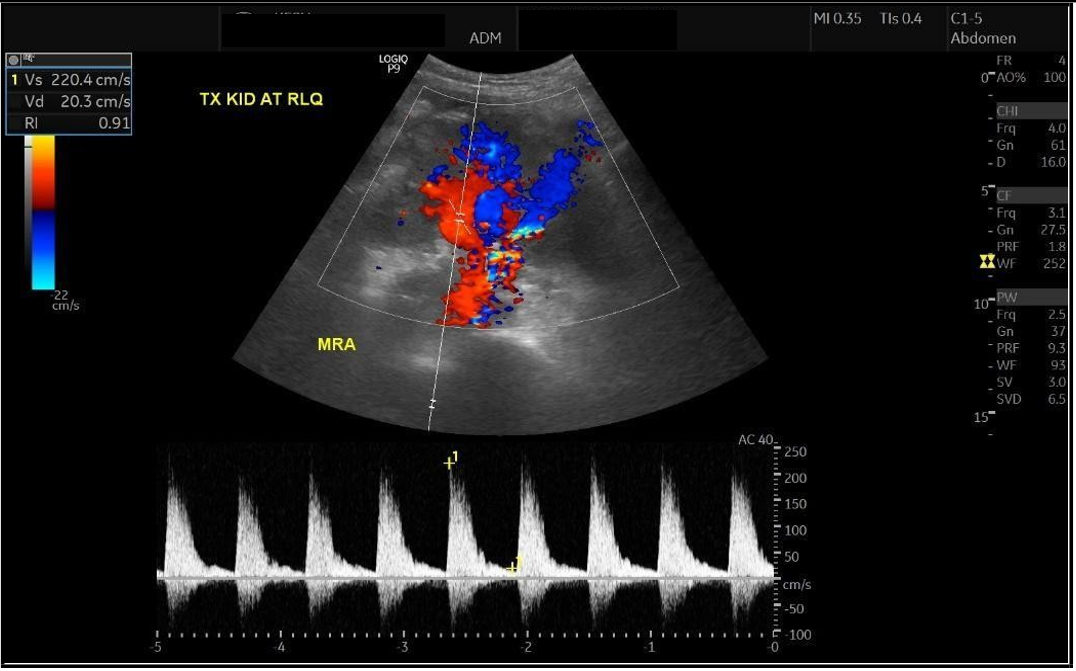

Renal Transplant In A Patient With May–Hegglin Anomaly: A Case Report And Literature Review

Corresponding Author: Sumayah Askandarani